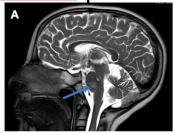

"Meningeal lymphatic architecture and drainage dynamics surrounding the human middle meningeal artery," was published in iScience on November 21st by Hiranmayi Ravichandran and colleagues.

"Meningeal lymphatic architecture and drainage dynamics surrounding the human middle meningeal artery," was published in iScienceon October 31st by Hiranmayi Ravichandran.